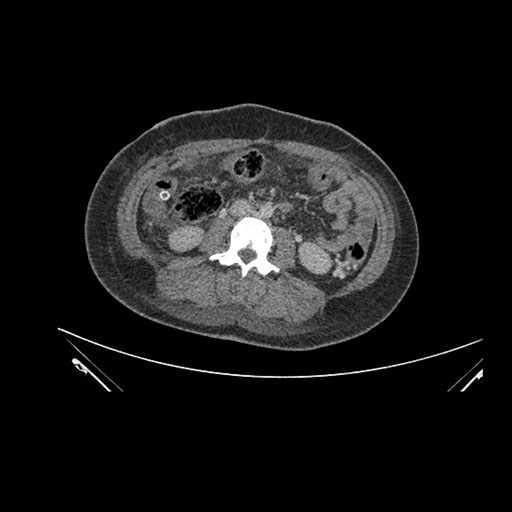

Imaging Analysis

Look through the patient's CT scan to identify any areas of concern for the necessary procedure.

Based on initial findings, which issue(s) would you be most concerned about?